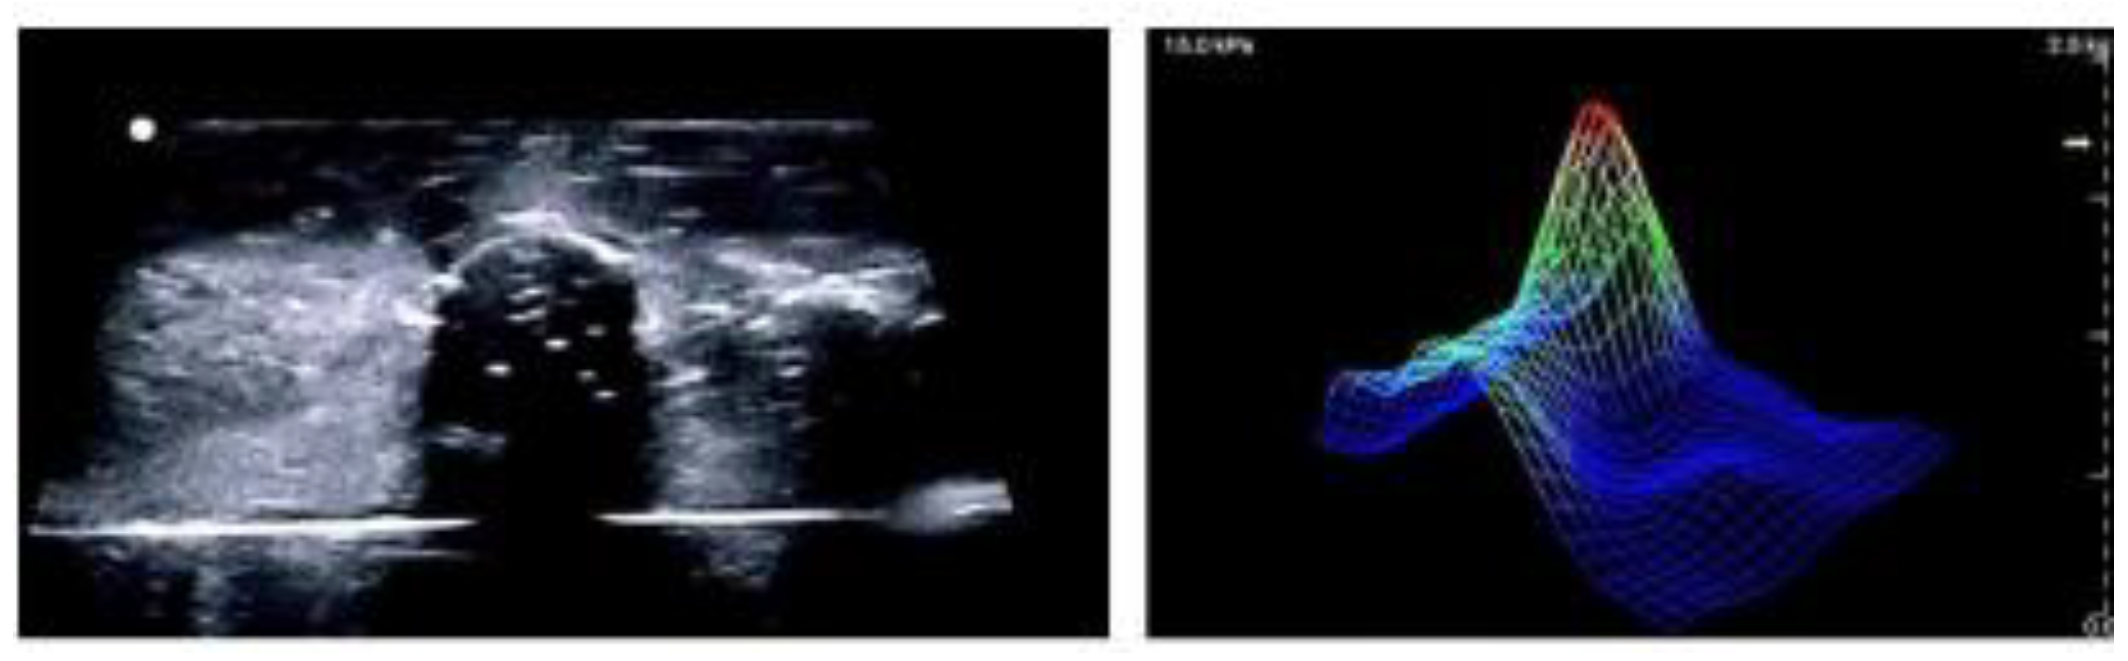

3.2. Current Work

Tactile imaging (capacitive sensor) has shown considerable promise in breast cancer diagnostics by differentiating benign from malignant lesions based on mechanical properties. As a non-invasive, radiation-free, and cost-effective modality, TI offers an appealing alternative to traditional imaging techniques. Recent research using breast phantoms has compared TI with US, demonstrating that while US achieves higher accuracy in lesion sizing, TI provides a faster and more intuitive screening experience with broader field-of-view coverage [109]. Figure 6 is a visual representation of how ultrasound and tactile imaging provide complementary information with ultrasound showing anatomical structure and tactile imaging representing tissue stiffness or elasticity. Ongoing clinical trials are assessing TI against clinical breast examinations to evaluate its diagnostic utility in real-world symptomatic populations [59].

Figure 6. Ultrasound image (left) and Tactile Imaging output (right) of a breast phantom, illustrating complementary structure and biomechanical data[109].